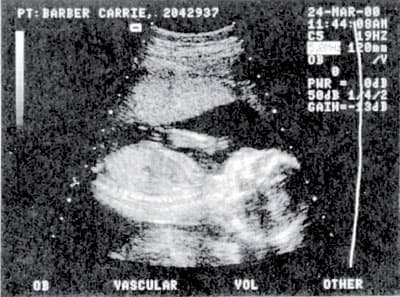

وأوضح أنه عندما يتبين أن في دم الأم كروموزوم ''Y'' يكون الجنين صبياً على الأرجح في حين أن غياب هذا الكروموزوم يؤكد أن الجنين أنثى. قال أنه بالمقارنة بفحص الدم فإن تحليل البول نجح في تحديد جنس الجنين بنسبة 41 في المائة فقط. يشار إلى أن التصوير ما فوق الصوتي يمكن أن يحدد أحياناً جنس الجنين في الأسبوع الحادي عشر من الحمل أحيانا لكن تبين أن النتائج تكون خاطئة بنسبة 40 في المائة. يذكر أن تحديد جنس الجنين بشكل مؤكد يكون عادة بين الأسبوعين الـ (18) والـ (22) من الحمل.